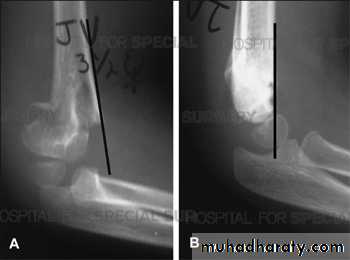

Supracondylar humeral fracture in children is one of the most common fractures seen in the pediatric orthopedic clinic setting worldwide. It's a fracture that occurs at the supracondylar area or the metaphysis of the distal humerus & accounts for 65.4% of upper extremity fractures in children .There are two types of supracondylar fractures in children according to direction of displacement of distal fragment i.e. extension type (97%) and flexion (3%).Immobilisation in an above-elbow backslab in 90 degrees elbow flexion with sling for 3 weeks. The backslab and sling should be worn under clothing (e.g. loose fitting shirt) and not through the sleeve

A gentle reduction can be achieved by an anterior push on the distal fragment as the elbow is flexed to 90 degrees

Requires urgent reduction and percutaneous pin fixation